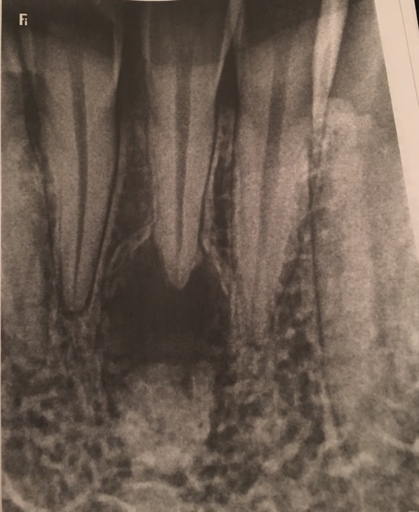

What can this be?

I went for a wisdom tooth removal but they found this space under tooth #24 after doing my X-ray examination.. I’m really scared that I might loose the tooth or have to have a tooth removed. I don’t have any pain with the tooth and no problems as to bleeding gums or any pain at all. I need some insight on what this could be? Or what’s going to happen next to this actual tooth..

I went for a wisdom tooth removal but they found this space under tooth #24 after doing my X-ray examination.. I’m really scared that I might loose the tooth or have to have a tooth removed. I don’t have any pain with the tooth and no problems as to...